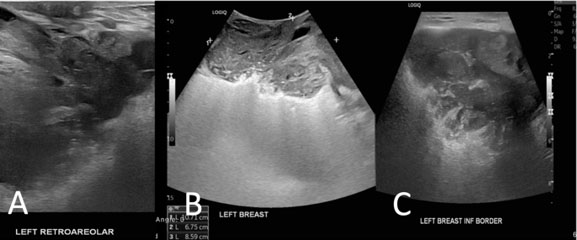

Previous work up few months ago was reviewed revealing an oval, circumscribed, heterogenous complex mass on the left breast, measuring around 10.7 × 6.8 × 6.8 cm at the left breast which is predominantly solid and with microcalcifications (Figure 2). Mammography was done revealing a large, irregular, complex mass occupying the entire left breast. An exophytic component through the lower inner quadrant was noted with diffuse skin thickening (Figure 3). Receiving hemoglobin of the patient is at 8 mg/dL which was subsequently managed with transfusion of blood products. The bleeding mass was also adequately controlled during the admission.

Figure 2: Ultrasound findings reveal a fungating wound, skin, and nipple thickening and retraction on the left breast. (A) Mass almost occupies the entire left breast and extends to the retroareolar region. (B) Oval, circumscribed, heterogenous, complex mass, predominantly solid with macrocalcifications ~10.7 × 6.8 × 8.6 cm. (C) Appears to extend to the pectoralis muscle.